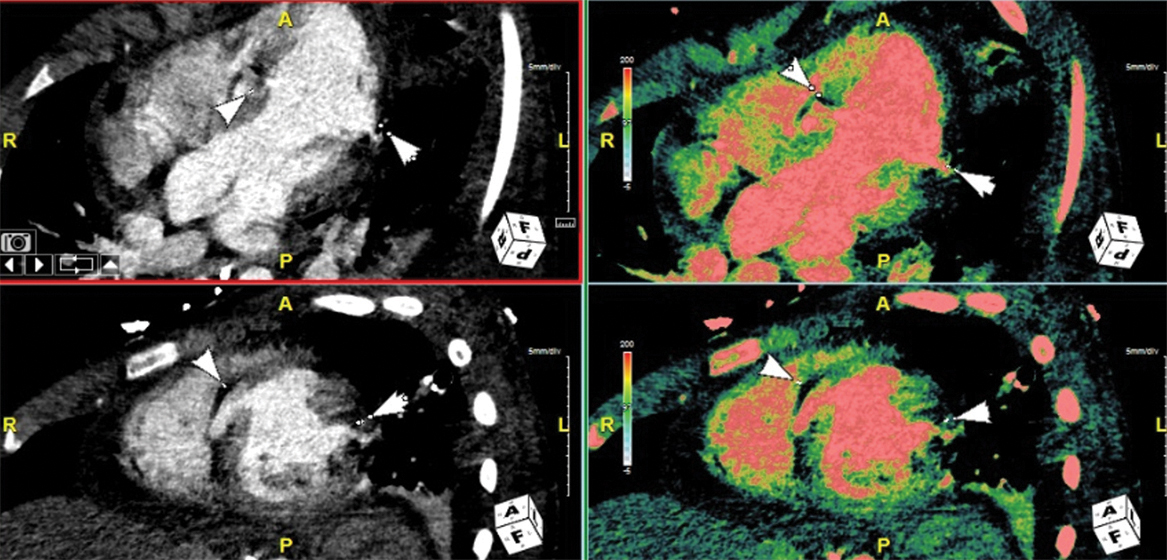

- AI-powered coronary plaque analysis is now routinely used in CT workflows at Plano and Dallas, offering noninvasive quantification and characterization of coronary plaque. This tool enables proactive prevention strategies, precise procedural planning, and effective monitoring of disease progression or response to therapy—bringing personalized, precision cardiology to the forefront of care.